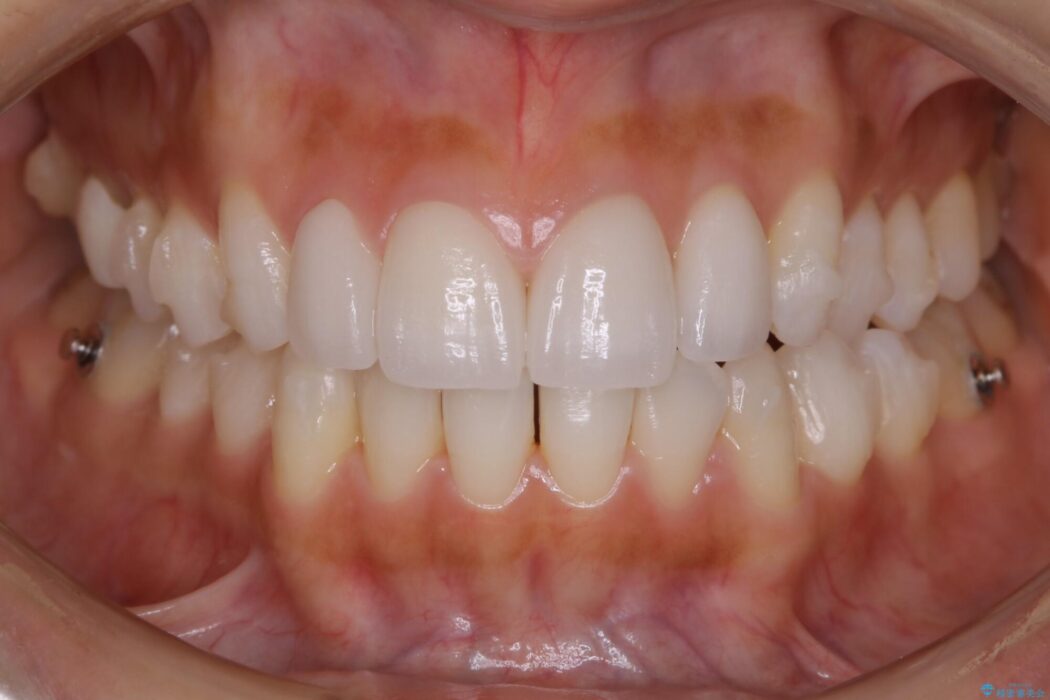

本症例ではセラミッククラウンのかぶせ物をした歯が複数ありました。

セラミック等の被せ物がある場合、それ自体の外形は矯正治療では変えられないため天然歯の移動に影響を与えてしまうことがあります。

加えてインビザラインでの治療上設定されるアタッチメント(歯の表面に付けるプラスチックの突起)が外れやすい場合が多く、歯の移動に対する力が不足する可能性があります。